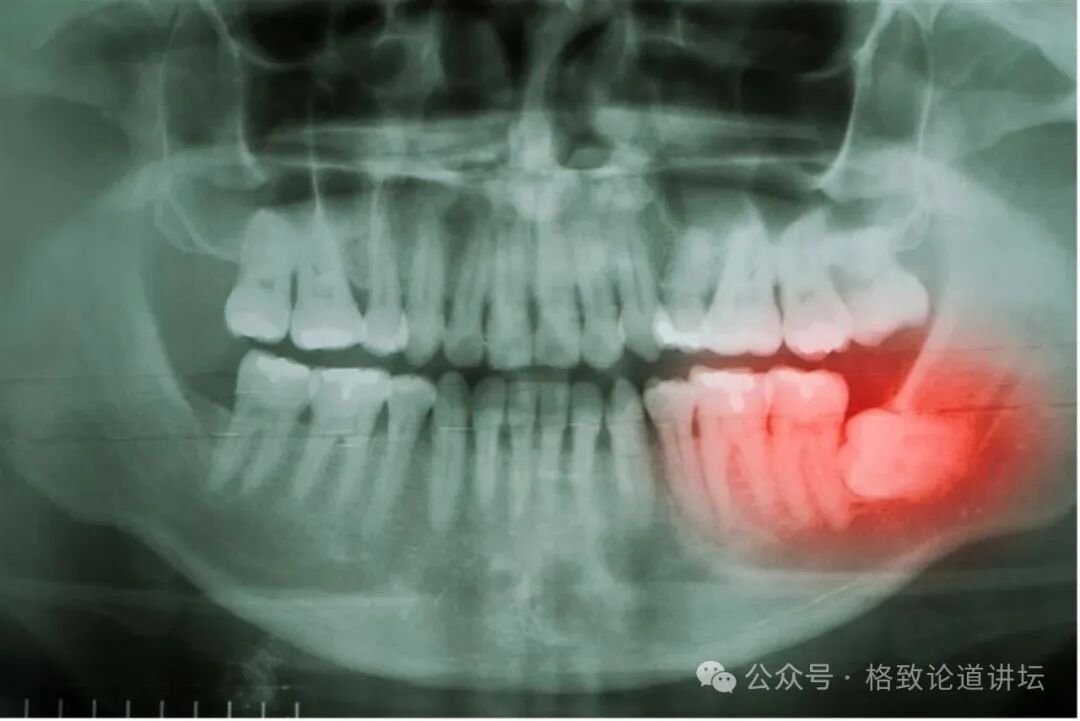

首先,我们带大家看的不是厨房里的煎炒烹炸技艺,也不是锅碗瓢盆工具,而是我们的牙齿。在x光的牙齿照片中,我们可以看到其中标红的这颗牙不太配合,横着长了。这颗牙叫智齿。为什么智齿的智是智慧的智?明明它是迟滞长出来,不应该用停滞的滞吗?

▲图片来源于网络

在传统上有这样一个说法:这颗牙齿是在20多岁、30岁左右才长出来的,而这个时间段人已经积累了相当的经验与学识,变得有智慧了,所以这个牙齿叫智齿。

智齿的名字好像可以这么理解,但听起来也不是特别合适,给人一种这颗牙齿是AI的错觉,直接插上来就聪明了,但有那么简单吗?没有。从植物学的视角来看,这颗牙齿跟我们人类祖先传承智慧是直接相关的。

所以,这个时候长出来的智齿作为备份工具出现,帮助人类祖先嚼叶子,嚼完了叶子,还能活下去,把自己的知识和经验传递给后代,把智慧传递给后代。从这个角度来讲,这颗牙齿叫智齿当之无愧。